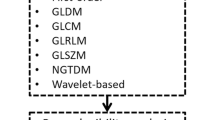

Five MR image features were suggested to be significantly different between pituitary adenoma and craniopharyngioma. Three texture features from contrast-enhanced T1WI (HISTO-Skewness, GLCM-Contrast and GLCM-Energy), two texture features from T2WI (HISTO-Skewness and GLCM-Contrast) showed significant differences between two types of tumors. Logistic regression analyses suggested GLCM-Energy from contrast-enhanced T1WI, HISTO-Skewness and GLCM-Contrast from T2WI could be taken as independent predictors. Moreover, HISTO-Skewness and GLCM-Contrast from T2WI were found to be significantly related to cystic change.

Nioche C, Orlhac F, Boughdad S, Reuzé S, Goya-Outi J, Robert C, et al. Lifex a freeware for radiomic feature calculation in multimodality imaging to accelerate advances in the characterization of tumor heterogeneity. Cancer Res. 2018;78(16):4786–9. https://doi.org/10.1158/0008-5472.can-18-0125.